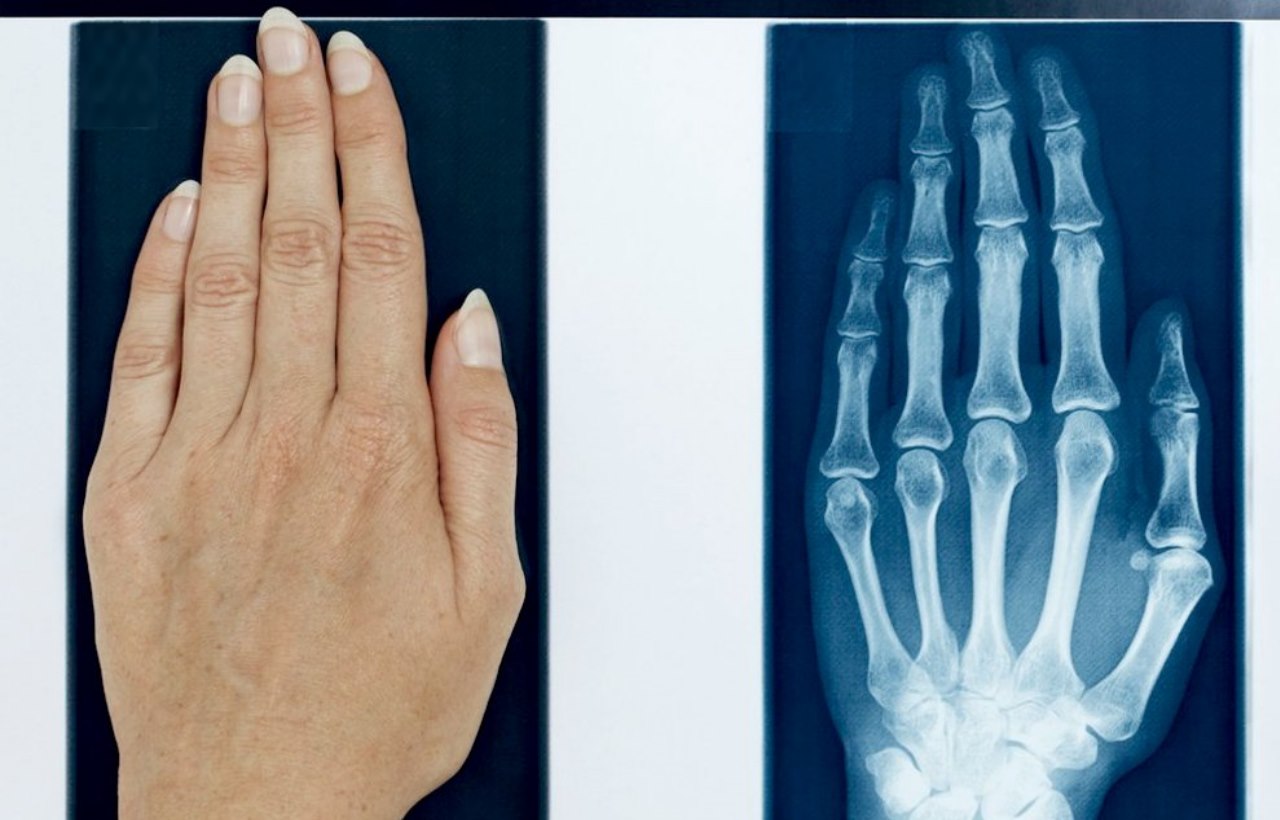

این سوال خصوصا در صد سال اخیر و با پیشرفت علومی همچون فیزیک و زیست شناسی بیشتر مطرح می شود. زیرا با پیشرفت فیزیک امواج مغناطیسی کشف شدند و کاشف به عمل آمد که در جهان طول موج هایی مثل امواج فرا بنفش، فروسرخ، گاما، اشعه ایکس و طول موج مرئی وجود دارد. امواجی مثل گاما، فرابنفش و اشعه ایکس بالاترین طول موج و امواج رادیویی پایینترین طول موج را دارد. پیشرفت علم دراین زمینه منجر به ساخت دستگاه آلات رادیولوژی، ماکروویو، رادیو و... شد. بعد ها بشر کشف کرد که تمام اجرام این کره خاکی به نوعی با امواج الکترومغناطیس در ارتباط اند.

تصویری از دست انسان که توسط اشعه ایکس در رادیولوژی گرفته شده